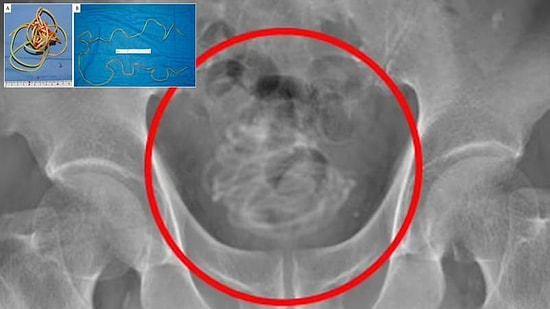

В Японии врачи обнаружили в пенисе 79-летнего мужчины двухметровую веревку от скакалки

В Японии в гениталиях 79-летнего мужчины, который обратился в больницу с жалобами на боль, была обнаружена 2-метровая скакалка.Неназванный мужчина, который был госпитализирован из-за болей, сказал, что почувствовал боль в паху, когда обратился в больницу.После того, как ему сделали рентген, врачи медицинского факультета Университета Докке, были ошеломлены, обнаруженным. В пенисе 79-летнего мужчины была обнаружена скакалка. В новостях, появившихся в британских СМИ, сотрудники больницы заявили, что 'не видели ничего подобного за всю свою карьеру'.